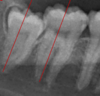

30

describe the relationship to the IAN canal

interruptioni of the white lines/lamina dura of the canal